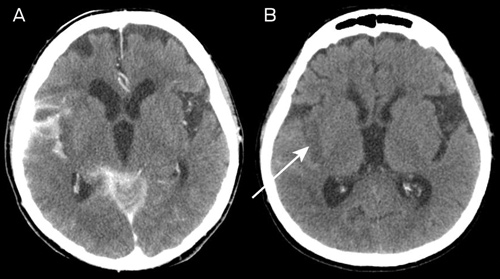

The NIHSS scores immediately after the procedure and at 24 hours were 17 and 8, respectively. A routine CT scan of the brain at 24 hours showed hyperdensity in the subarachnoid space (which had largely resolved on further CT imaging by Day 11) as well as infarction, predominantly within the posterior insular cortex (Box 4).